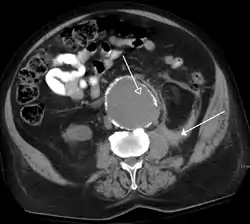

![]() تصویر گرفته شده توسط سی تی اسکن که ضایعهای در آئورت را نشان میدهد. | |